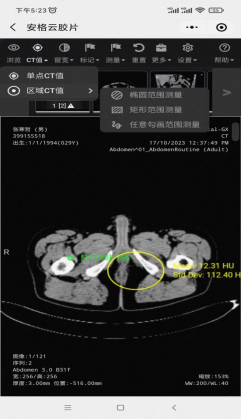

④安格云数字影像患者端提供多路径入口。图像浏览操作端内置丰富图像诊断工具,如:CT值测量(唯一点对点所见即所得的精准CT值测量方式),罕有的容积重建功能等等、方便进行分享、下载、会诊、远程诊断。